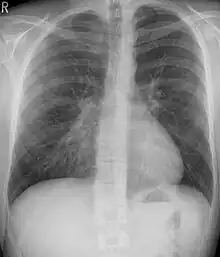

Pectus excavatum is initially suspected from visual examination of the anterior chest. Auscultation of the chest can reveal displaced heart beat and valve prolapse. There can be a heart murmur occurring during systole caused by proximity between the sternum and the pulmonary artery.[15] Lung sounds are usually clear yet diminished due to decreased base lung capacity.[16]

Chest x-rays are also useful in the diagnosis. The chest x-ray in pectus excavatum can show an opacity in the right lung area that can be mistaken for an infiltrate (such as that seen with pneumonia).[20] Some studies also suggest that the Haller index can be calculated based on chest x-ray as opposed to CT scanning in individuals who have no limitation in their function.[21]

Pectus excavatum is differentiated from other disorders by a series of elimination of signs and symptoms. Pectus carinatum is excluded by the simple observation of a collapsing of the sternum rather than a protrusion. Kyphoscoliosis is excluded by diagnostic imaging of the spine, wherein pectus excavatum the spine usually appears normal in structure.